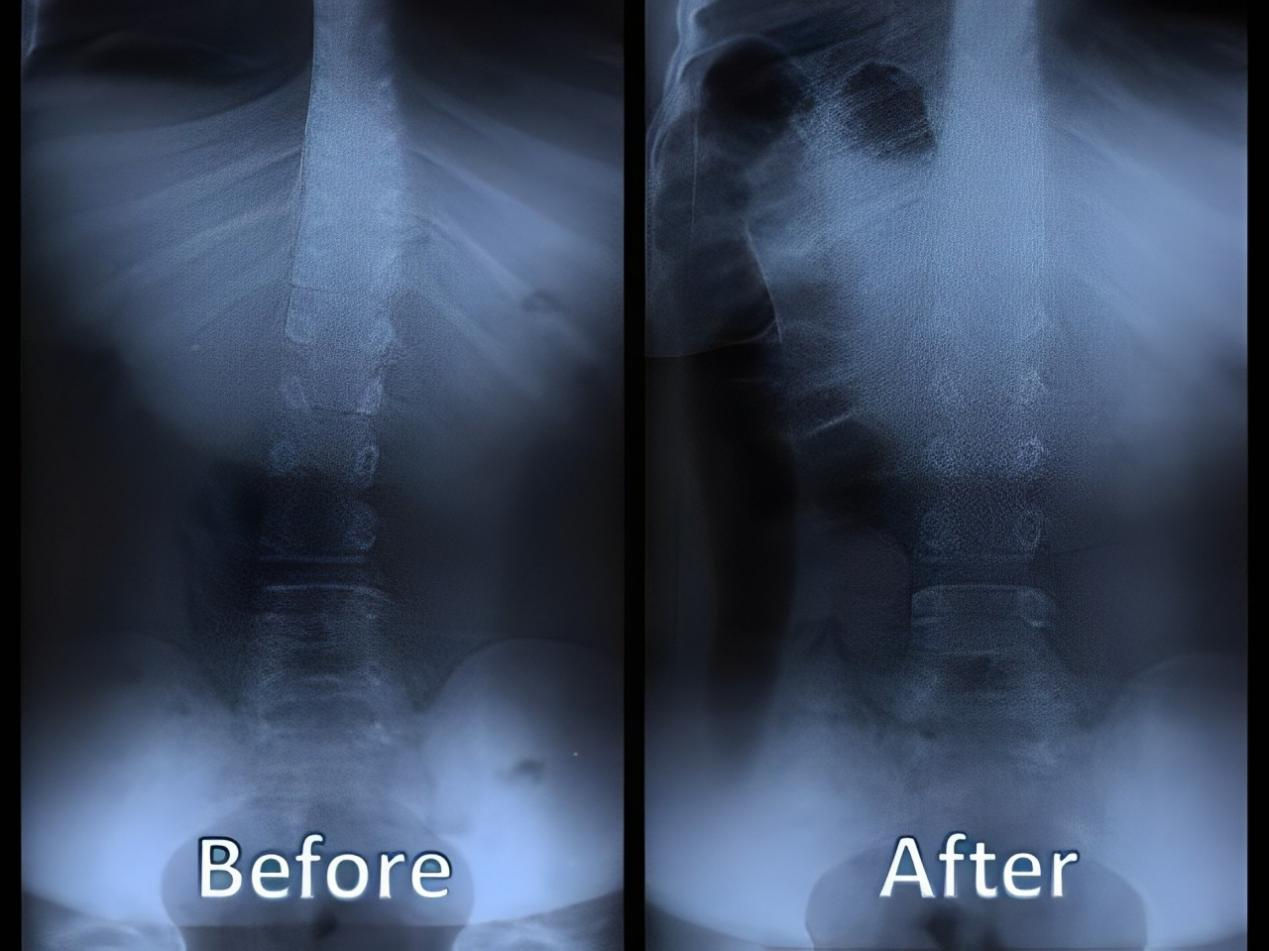

五、矯正完和矯正后的對比案例: